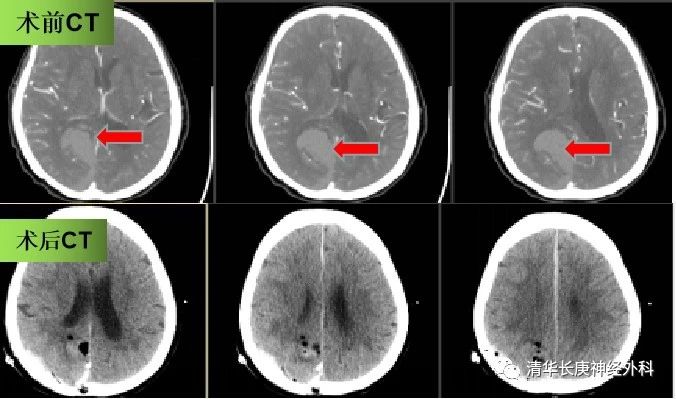

68岁的马女士,3小时前突发头痛,伴恶心、呕吐,家属陪伴下就诊于外院,头颅CT提示右顶枕脑出血,转诊至我院后,予患者复查脑血管CT成像检查,排除脑肿瘤和血管畸形等,急诊行开颅血肿清除术,患者术后1天神经功能已基本恢复正常,日常活动无明显影响。这种脑叶出血的患者,若未发生脑疝等严重情况,往往手术效果良好,病情允许情况下,建议积极手术治疗。

图3 患者手术前后头颅CT,血肿清除满意